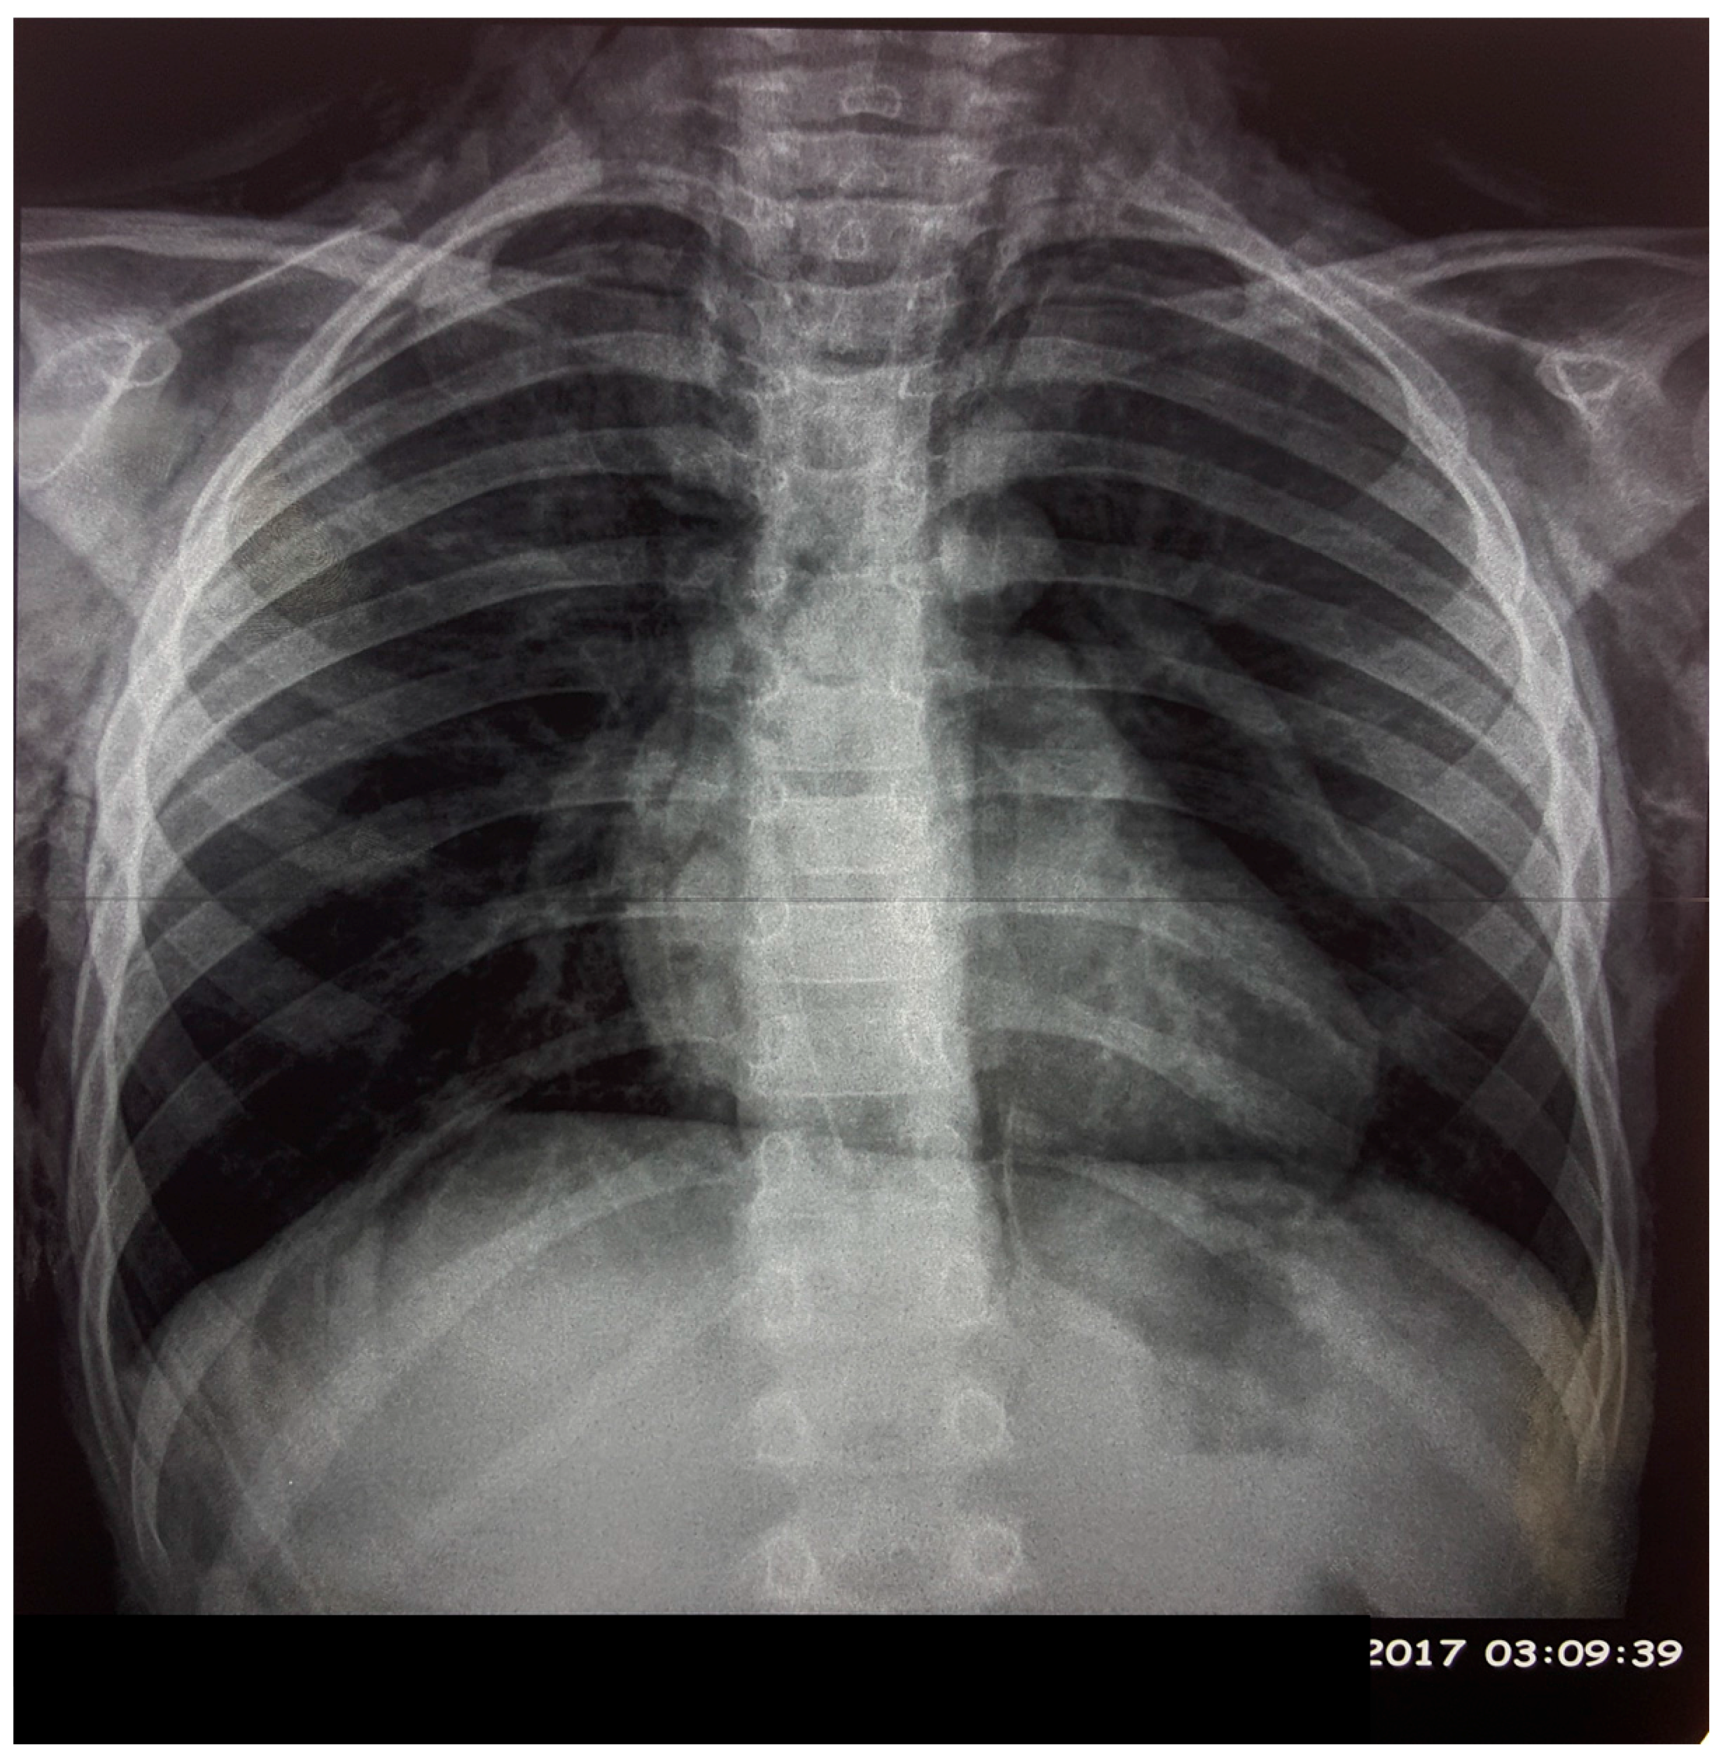

2. Case Presentation